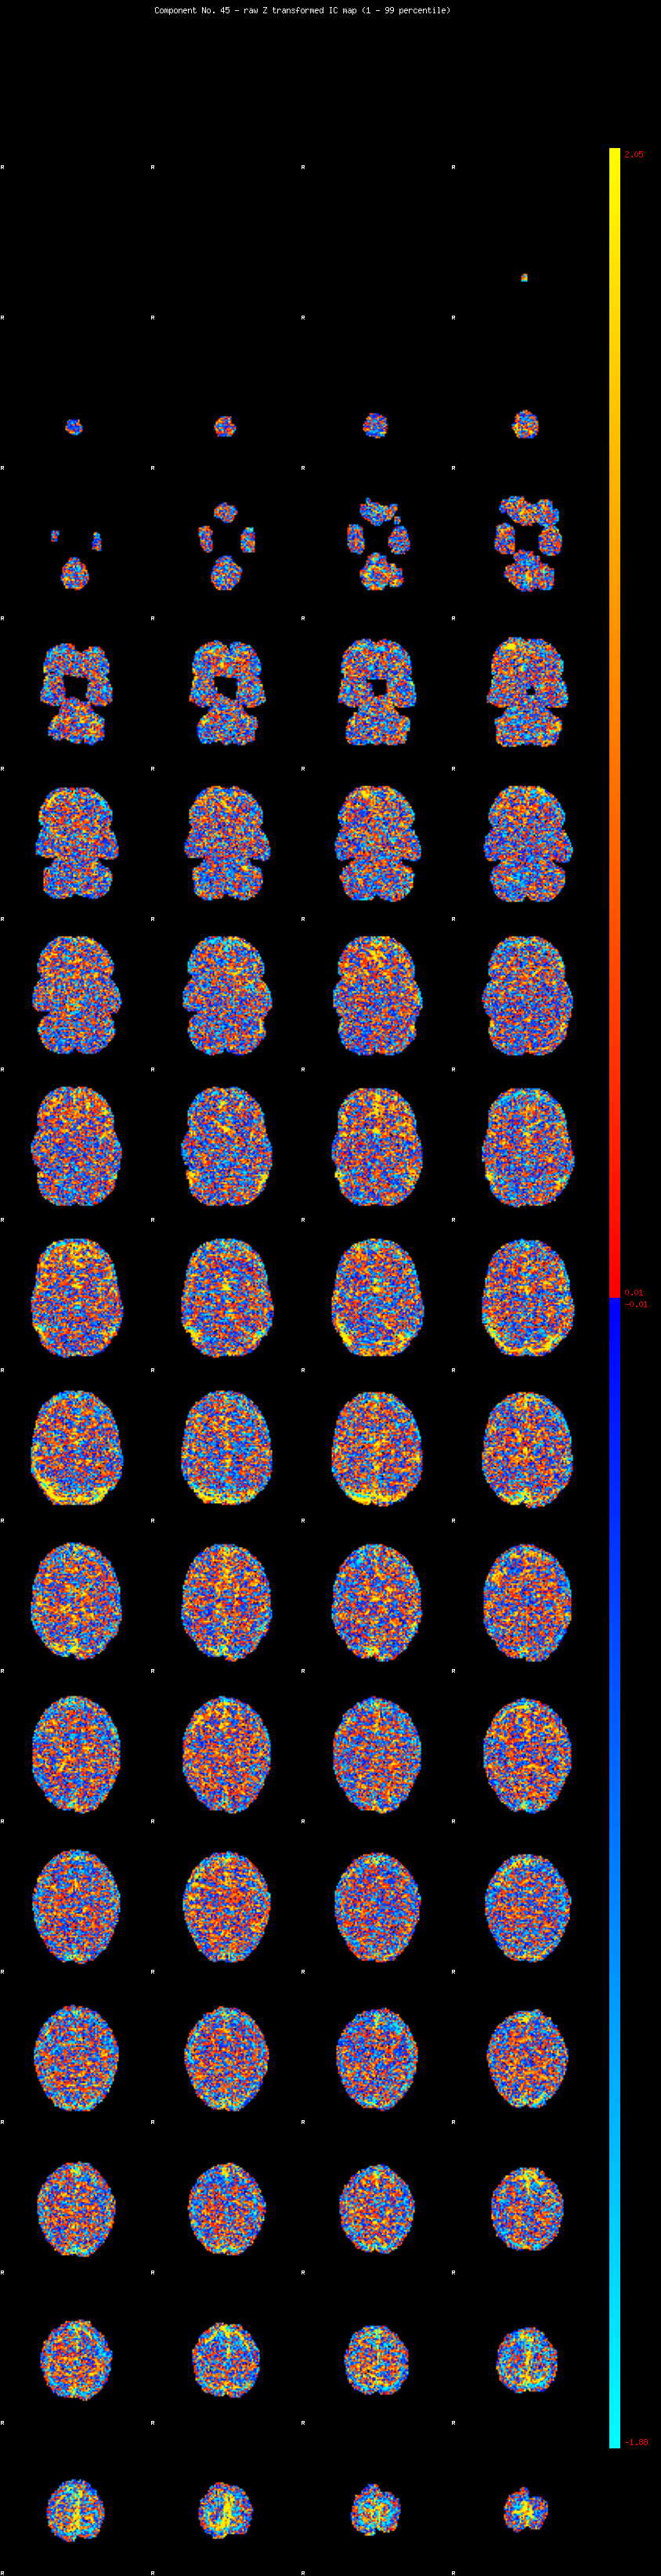

IC_45 Mixture Model fit

Means : -0.000000 2.717844 -2.404956

Vars : 1.000000 2.839340 1.340366

Prop. : 0.944595 0.034782 0.020623